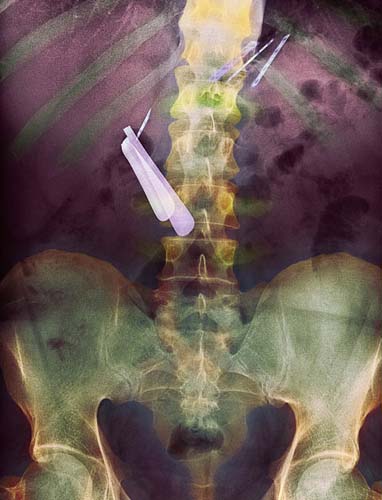

Jilet yutmuş bir akıl hastasının röntgeni...